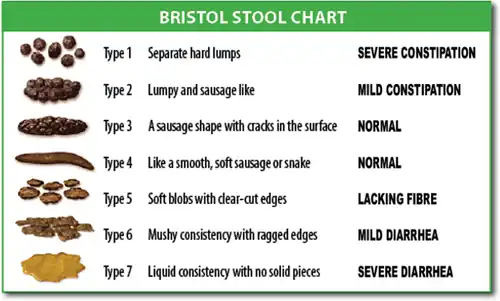

The diagnosis is typically made based on a person's description of the symptoms. Bowel movements that are difficult to pass, very firm, or made up of small hard pellets (like those excreted by rabbits) qualify as constipation, even if they occur every day. Constipation is traditionally defined as three or fewer bowel movements per week.[15] Other symptoms related to constipation can include bloating, distension, abdominal pain, headaches, a feeling of fatigue and nervous exhaustion, or a sense of incomplete emptying.[40] Although constipation may be a diagnosis, it is typically viewed as a symptom that requires evaluation to discern a cause.

Distinguish between acute (days to weeks) or chronic (months to years) onset of constipation because this information changes the differential diagnosis. This in the context of accompanied symptoms helps physicians discover the cause of constipation. People often describe their constipation as bowel movements that are difficult to pass, firm stool with lumpy or hard consistency, and excessive straining during bowel movements. Bloating, abdominal distension, and abdominal pain often accompany constipation.[41] Chronic constipation (symptoms present at least three days per month for more than three months) associated with abdominal discomfort is often diagnosed as irritable bowel syndrome (IBS) when no obvious cause is found.[42]

- Lumpy or hard stools in at least 25% of defecations